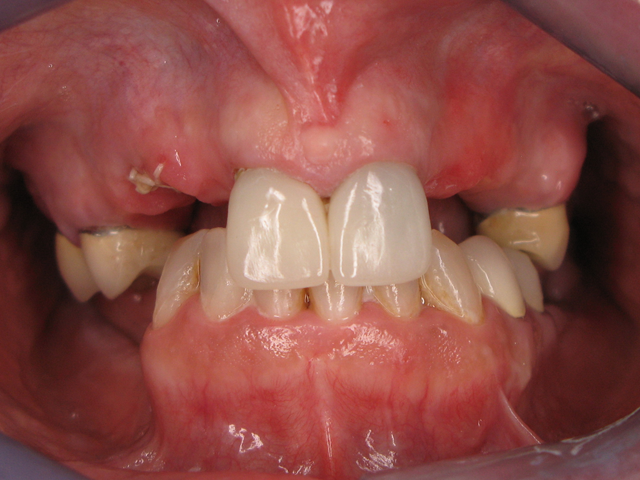

The patient no longer wanted the partial denture that she had basically learned to live with for many years; she wanted a “fixed” solution. Teeth #s 3, 4, 8, 9 and 13 were to be prepped and were our only abutments. (Figs. 1 & 2)

Fig. 1                                                                                               Fig. 2

My initial thought was to fabricate two bridges but I did not trust so few abutments and the multiple pontic spans. The doctor and I decided that a round house bridge (full upper restoration) was our best plan for success.